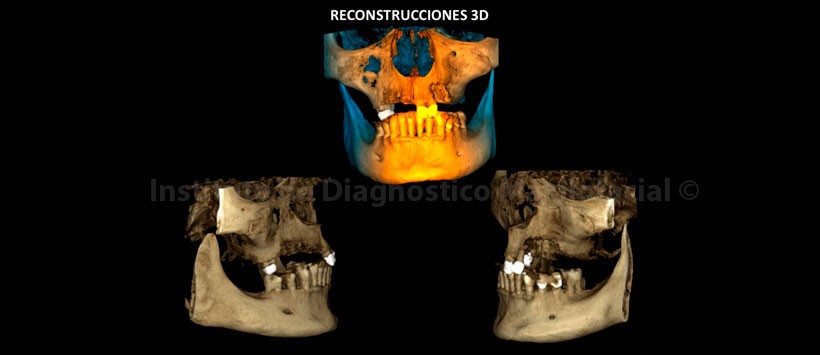

En las reconstrucciones 3D se representa la lesión ósea que involucra los lechos alveolares de piezas 2.3 y 2.4 y además la presencia de secuestros óseos (Figura 9,10 y 11).

Conclusión: Signos tomográficos sugerentes de Osteonecrosis maxilar por bifosfonatos